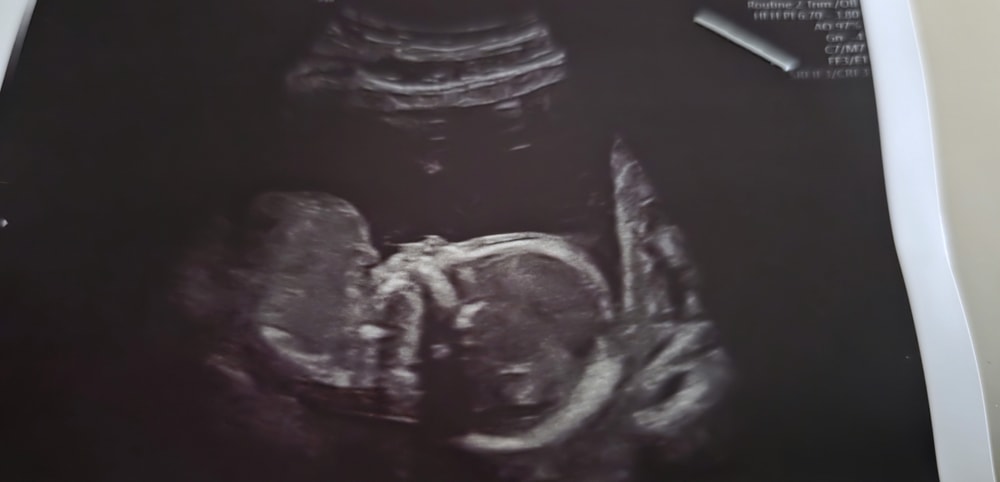

УЗИ 18.2 недель

Приезжал муж, ходили сегодня на УЗИ. Правда он мало чего разглядел, но крохотную пяточку и ладошку увидел. Разбудили дочку, врач сказала "Малышка устраивает бунт на корабле"😊я ощущала ее аккурат пиночки в датчик. Теперь я знаю, где ее голова, а где ножки.